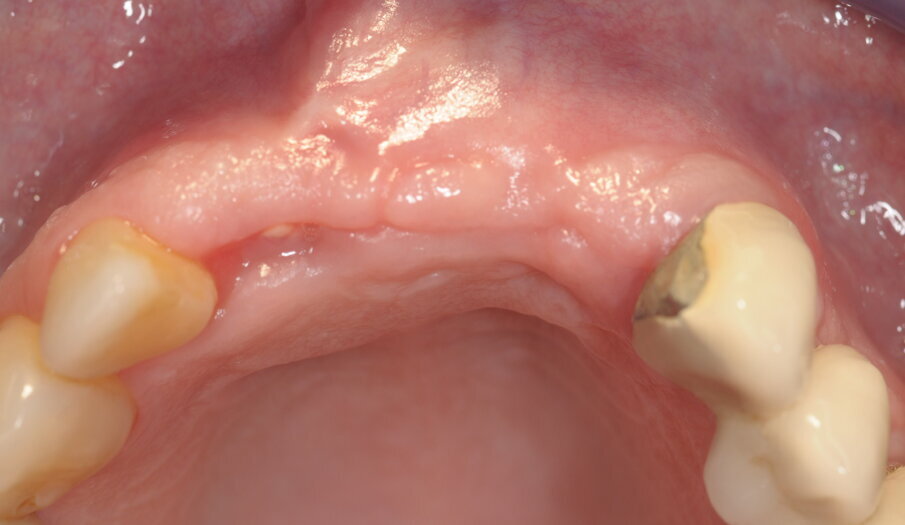

I risultati della guarigione a 9 mesi (Figg. 13, 15).

Fig. 15 - Valutazione sito rigenerato in visione occlusale.

Fig. 20 - Scopertura degli impianti.

Fig. 22a, 22b - Valutazione dei tessuti duri e molli perimplantari.